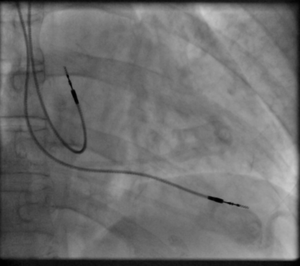

وأثناء عملية التركيب هذه يقوم الطبيب بمراقبة حركة السلك من خلال شاشة تلفزيونية تحت الأشعة السينية لوضع السلك الكهربائي في مكانه المحدد بالقلب.